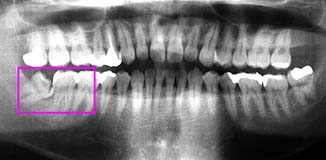

初診時 パノラマ 「8 拡大図 抜去 術式

下顎左側に埋伏した智歯が認められる

35歳 女性

レントゲンで見る以上に骨が歯冠部分を覆っている 周囲骨削除の上、歯冠カット

主訴は、|12の腫脹。

初診時口腔内およびX線所見:

主訴の|12は、歯根中央部の崩壊に伴う炎症が存在した。それ以外にも6|の 根尖病巣による腫脹が認められたが、清掃状態は比較的良好で、「8の埋伏を認めるも 臨床症状はないように思われた。

処置および経過:

上顎の治療を終了後メインテナンスに移行して約1年経過したころより、「8部の疼痛を訴えるよ うになった。

「7遠心の歯肉腫脹を起こすに至って、切開・排膿を試みると同時に探針で「8の埋伏状態を探った が、歯冠を触知することが難しくほとんど"完全埋伏歯"に近いことが疑われた。 ほとんど"完全埋伏歯"であることから、当初は、「7遠心根に歯石が沈着して起こした炎症を 疑ってしばらく経過を観察することとしたが、炎症は軽快することなく再び排膿を伴う腫脹を 起こしたことを契機として抜歯を決断。

歯冠のほんの一部が露出した埋伏歯であることから、周囲骨を大きく削合して、通例に従って 歯冠カットのうえ抜歯を行った。術後の経過は良好。

考察:

歯肉の上に顔を出した埋伏歯はほとんど抜歯の対象となるが、骨内に完全に埋伏した 智歯は炎症を起こさない限り抜歯の対象となることは少ない。しかし、わずかといえども 歯肉の隙間を介して口腔内と交通した場合には炎症を起こすことも決して稀なことではない。 ひとたび炎症を起こすようになった智歯はいつか抜歯しなくてはならない運命にあるといえる。

本症例の場合は、周囲骨の削合に結構時間を要したが、幸いにも歯根形態が単純であった ので比較的容易な症例であった。